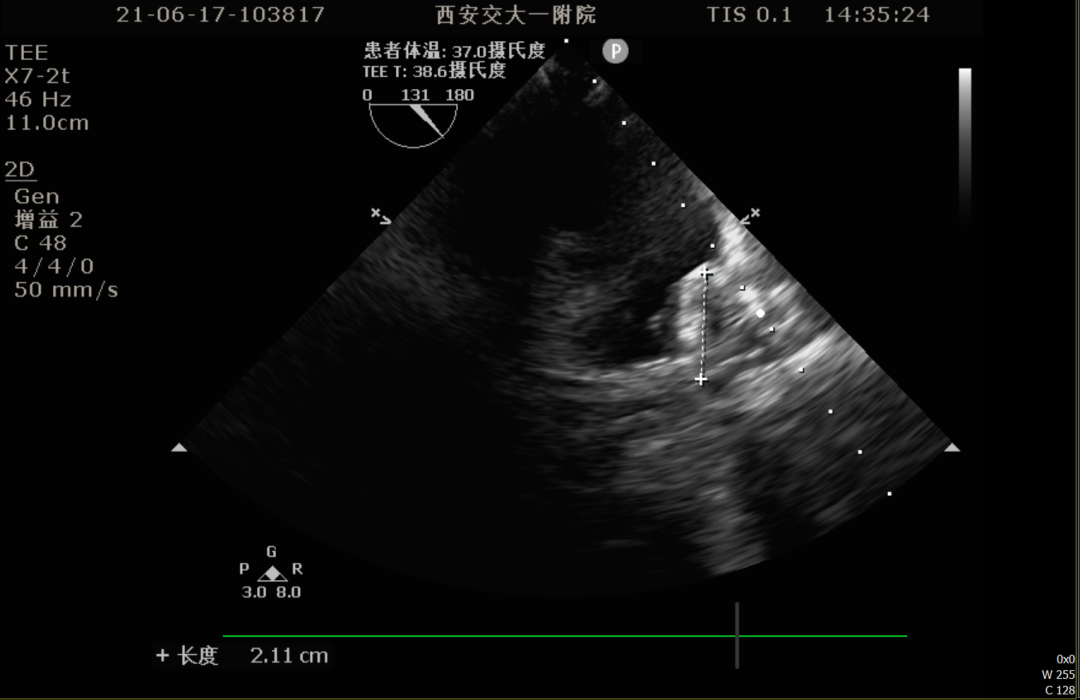

86°TEE

TEE测量左心耳数据:

TEE测量结果:

该患者左心耳开口较小,呈反鸡翅型,开口处即反折,同时内部梳状肌发达,且深度较浅,因此手术难度偏大,术前安排进一步CT评估以协助制定手术策略。